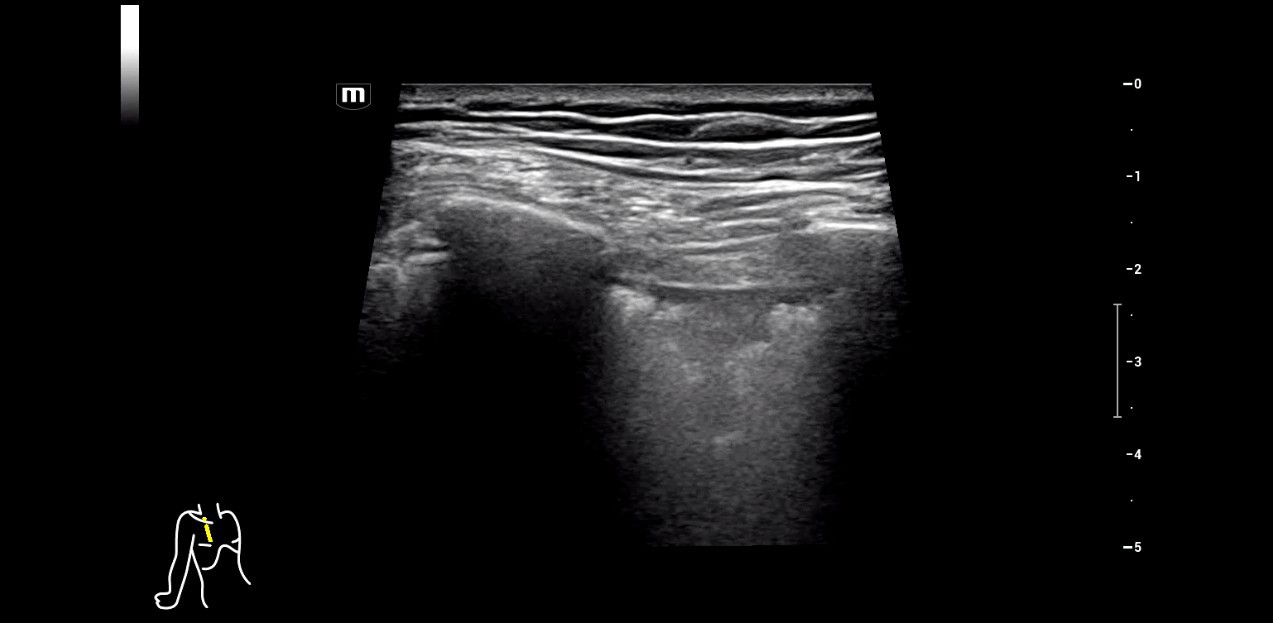

DarÞber hinaus sch?tzt Seibel auch die hervorragende Bildaufl?sung im Nahfeldbereich. Als erfahrener An?sthesist wird er zuweilen auch schmerztherapeutisch t?tig und nutzt das Ultraschallbild, um periphere Nervenblockaden zur postoperativen Schmerztherapie punktgenau zu platzieren. Dabei brauche es ?eine gute Qualit?t auf der Linearsonde, um die Injektionsnadel sicher ans Ziel zu fÞhren.â